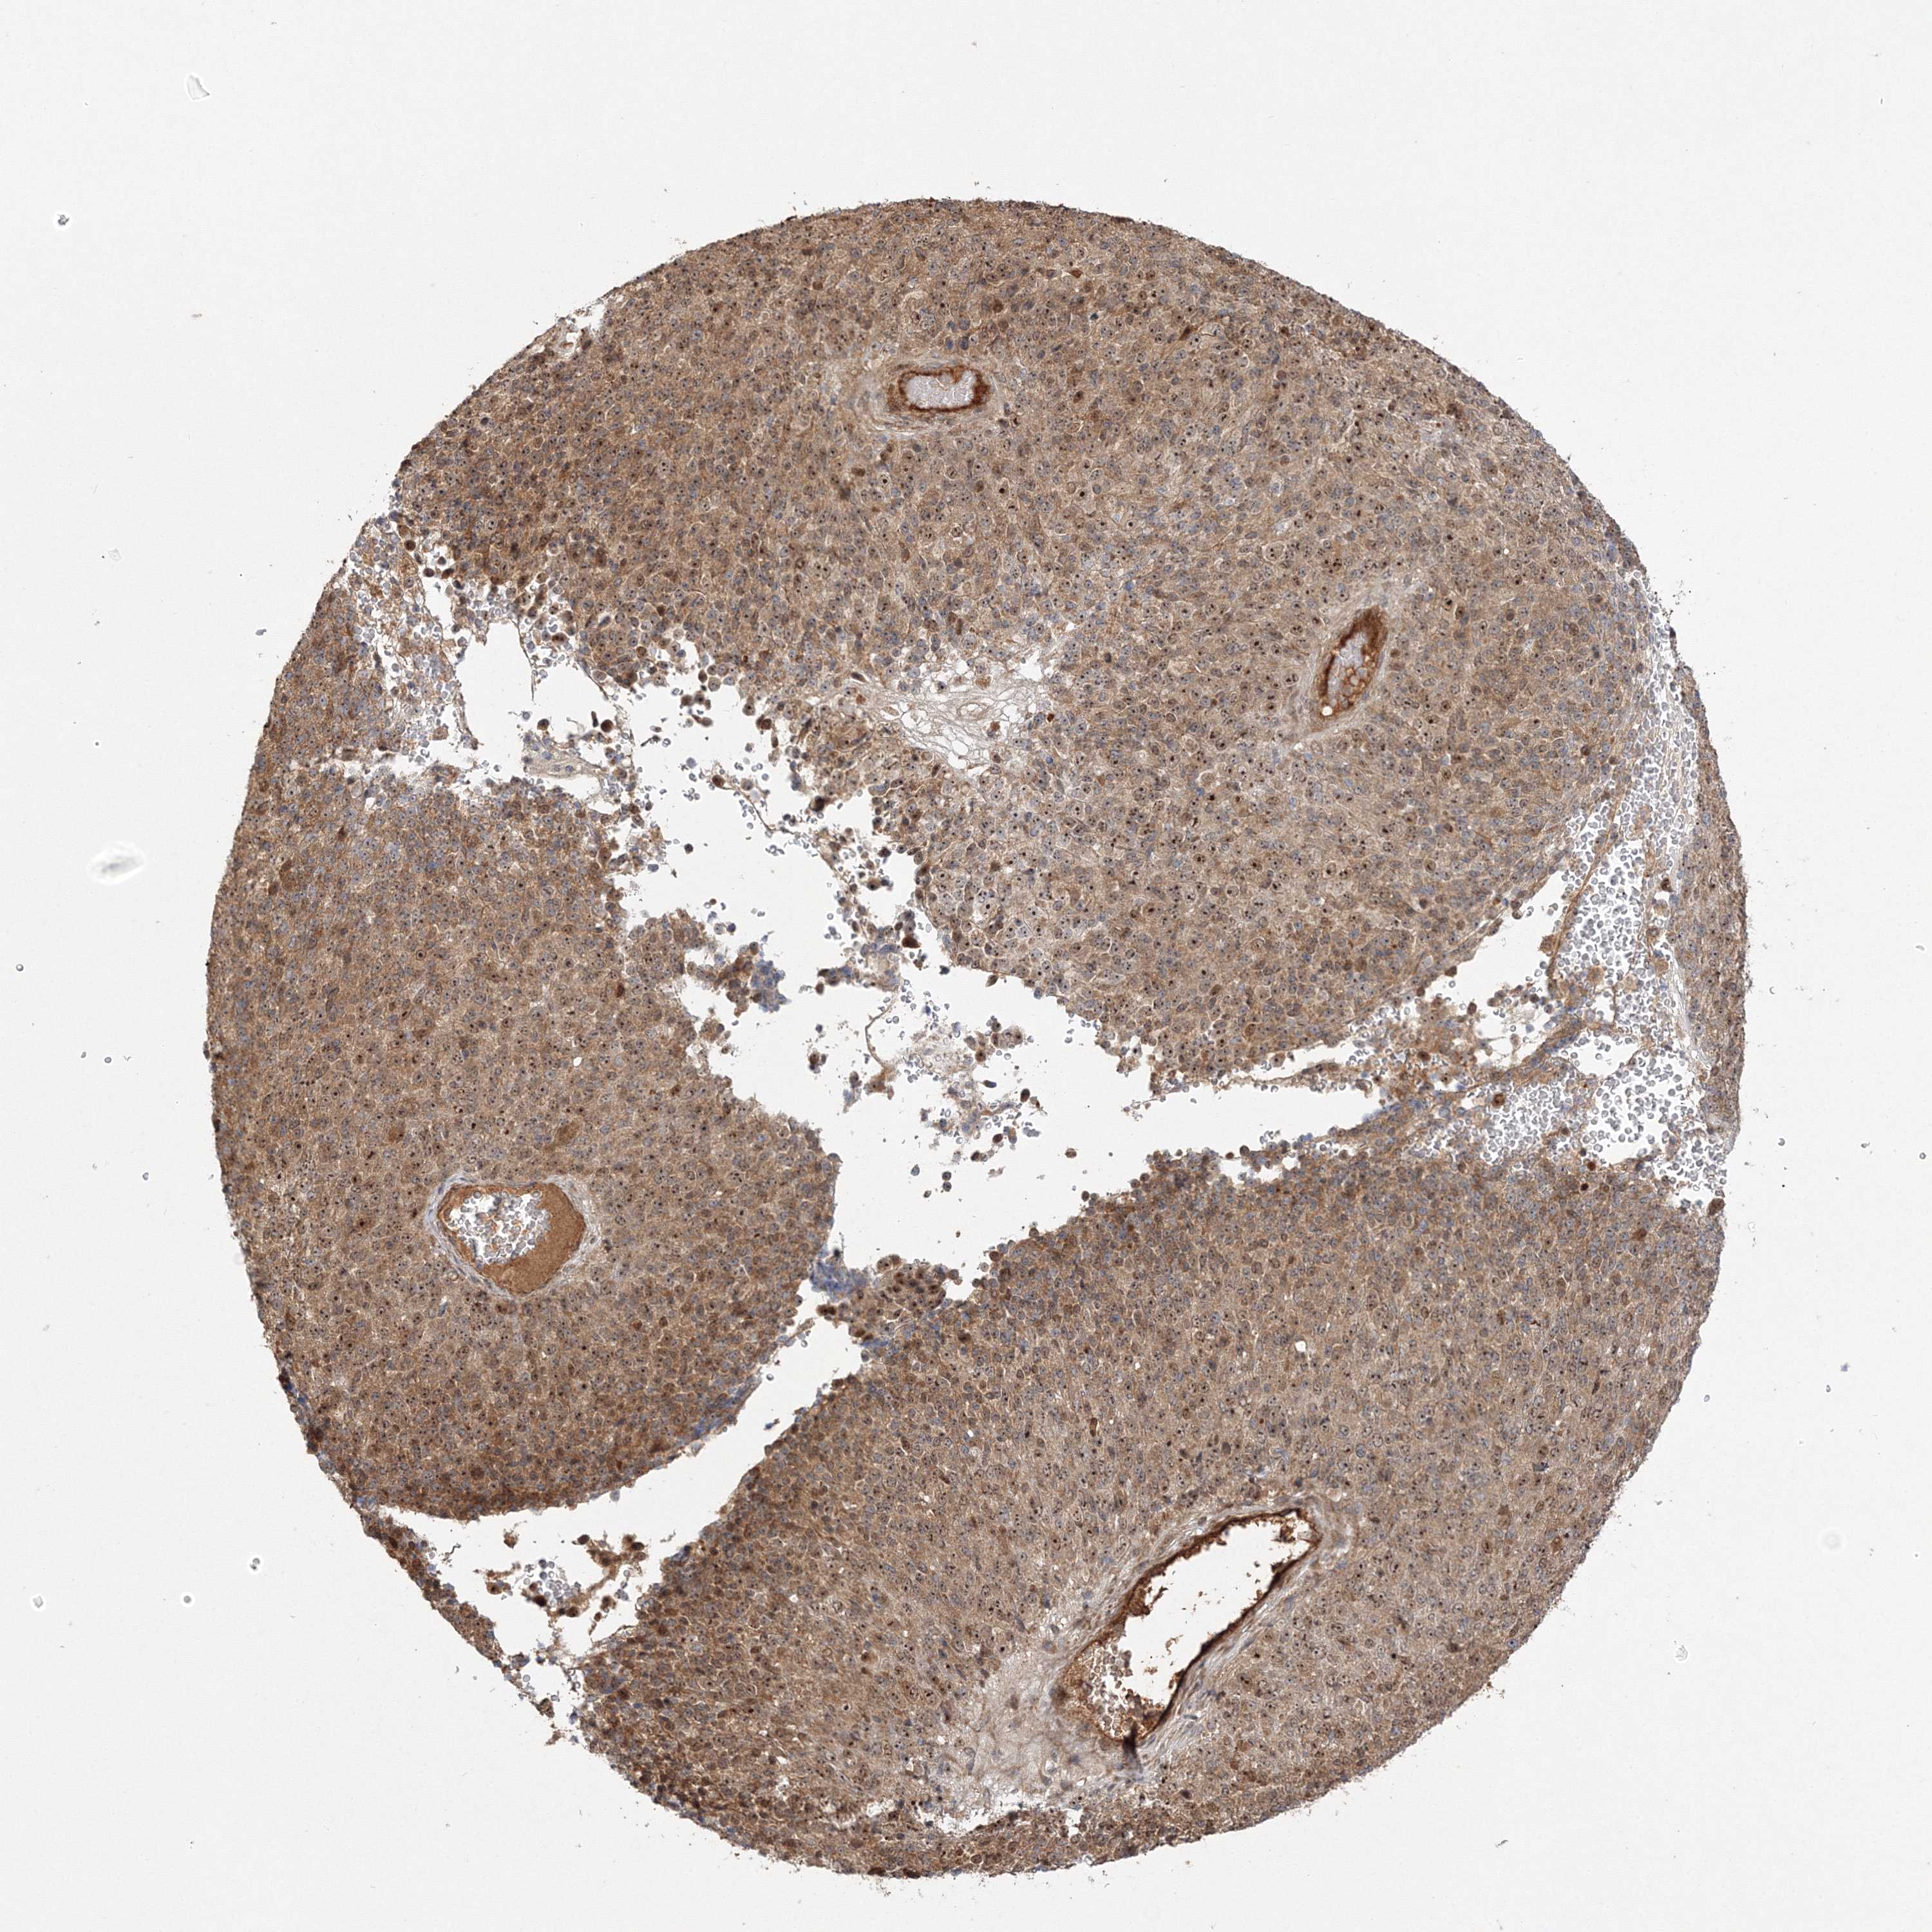

MELANOMA - Protein expressioni

A mouse-over function shows sample information and annotation data. Click on an image to view it in a full screen mode. Samples can be filtered based on level of antibody staining by selecting one or several of the following categories: high, medium, low and not detected. The assay and annotation is described here.

Note that samples used for immunohistochemistry by the Human Protein Atlas do not correspond to samples in the TCGA dataset.

Antibody stainingi

Antibody staining in the annotated cell types in the current human tissue is reported as not detected, low, medium, or high, based on conventional immunohistochemistry profiling in selected tissues. This score is based on the combination of the staining intensity and fraction of stained cells.

Each image is clickable and will lead to virtual microscopy that enables deeper exploration of all samples and also displays staining intensity scores, fraction scores and subcellular localization as well as patient and tissue information for each sample.

Antibody HPA036295

Antibody HPA036296

Staining

High

Medium

Low

Not detected

Intensity

Strong

Moderate

Weak

Negative

Quantity

>75%

75%-25%

<25%

None

Location

Nuclear

Cytoplasmic/membranous

Cytoplasmic/membranous,nuclear

Malignant melanoma, NOS

Malignant melanoma, Metastatic site